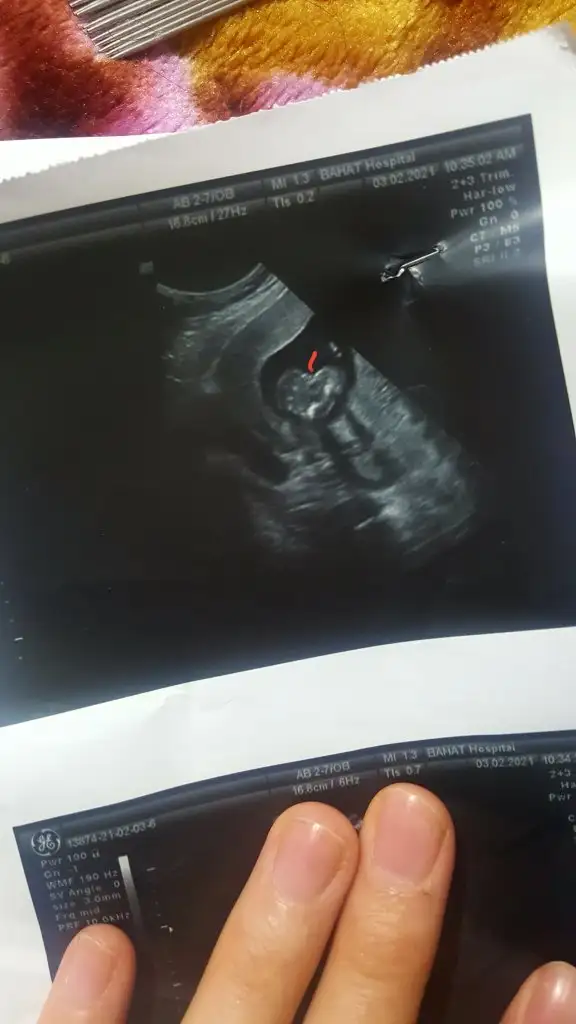

O nasil bi doktormus ya 16 haftalik olmussun ya kordon caddie Bacak arasinda net goremedi ondan yuzde 51 dedi yuzde 51 ne Demek ay bence kizda degildir ozaman bana oyle geliyo kesin net gorseydi 80/90 derdi bence Sen baska doktora git bence bana devlet 90% kiz demisti 20 haftalikken dusun yaniYa kızlar 16 +4 günlük devlet kız gözüküyor dedi bugünde özel 100/51 kiz dedi